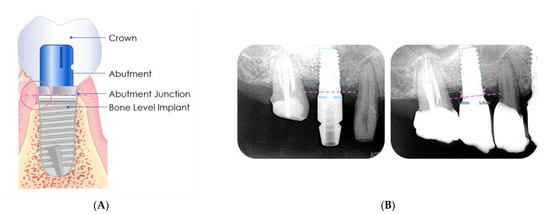

The baseline of the reference point was located at the junction between the fixture and the abutment. The vertical height distance from the fixture–abutment junction to the margin of the crestal bone was measured (Figure 2) and recorded in mm.

The amount of change in the MBL was measured by comparing the mean MBLs before prosthetics delivery and after different follow-up periods. The average change in the mesiodistal bone levels was calculated for each dental implant.